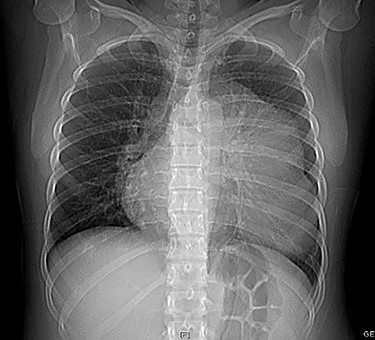

A 40-year-old female patient with a history of hypothyroidism was presented to the hospital with 5-day long flu-like symptoms (malaise, rhinorrhea and chills) along with cough and fever. By the time of her admission, she presented with dyspnea and an oxygen saturation level of 85%. On examination, the temperature was 37°C, respiratory rate 24 cycles/min, pulse rate 98 bpm, blood pressure 105/60 mm Hg. Rales were present at both pulmonary bases and mild abdominal pain was found on palpation over the upper right quadrant without peritoneal irritation signs. A chest x-ray was performed showing a radiopaque image at the left side of the cardiac silhouette from the second and seventh costal arc, deviation of the airway to the right side, and absence of pleural effusion (Fig. 1). A CT scan revealed a heterogeneous extrapulmonary multiloculated and predominantly fluid density lesion. It was located at the anterior mediastinum with left lateral extension. On intravenous contrast administration, wall enhancement of the lesion was observed, without pericardium involvement (Fig. 2).

Chest x-ray showing a radiopaque image at the left side of the cardiac silhouette from the second to seventh costal arc and deviation of the airway to the right side without pleural effusion.